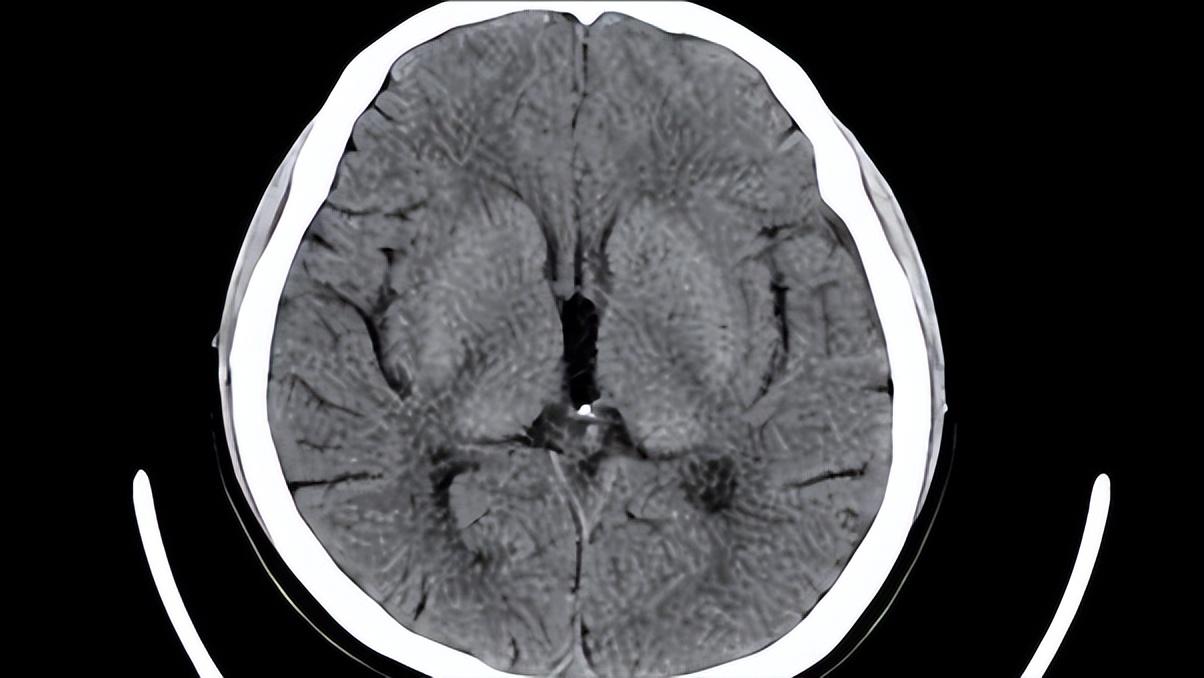

谁料,CT结果显示腔隙脑梗和脑萎缩。看到赤裸裸的几个大字,大爷甚至手都在发抖,没想到自己得了这么严重的病,脑梗都算了,直接都萎缩了。

腔梗是一种直径小于2厘米,很小的梗死灶。这种梗死一般发生在大脑深部的基底节区和脑干等部位,而所涉及到的动脉也一般是细小动脉,被称为深穿支。这些小动脉大多是脑动脉的末梢,因此也被称为终末支。

因为深穿支特殊的部位和体积,所以动脉供血范围其实是很有限的,因而单独一支发生阻塞只会引起很小范围脑组织的缺血性坏死,即是腔梗。

但是我们要注意的是,可不是所有腔梗患者都会有症状哦,只有它恰好发生在累及到重要神经通路的动脉末梢才会有明显的临床表现。

大脑亦是如此,到了老年时,它也会逐渐衰老和退化。因此大脑中各种各样的脑细胞就会逐渐减少。过往统计研究,当我们70岁时,这些脑细胞已经至少减少了30%。所以内容物减少了,那么质量和体积减少也是正常的。这就是生理性脑萎缩,一般CT片子下都是脑回变窄,脑沟加深等字眼。